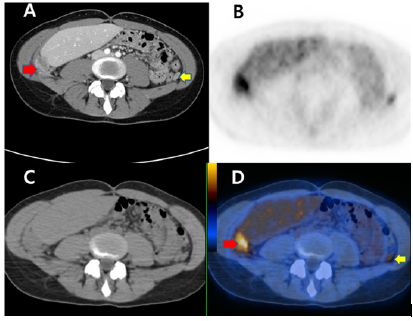

Figure 3: Abdominal pelvic CT with contrast enhancement(A) showed amorphous enhancing soft tissue portion in pelvic cavity. And any definite abnormal finding in the both ovary could not find on the CT. F-18 FDG PET-CT (B, C, D) showed intense FDG uptake in the pelvic lesions with amorphous enhancing soft tissue on the CT. And this could be interpreted as metastatic lesions in the pelvis.

Figure 4: Abdominal pelvic CT with contrast enhancement(A) showed enhancing small peritoneal nodule in left abdominal cavity and large peritoneal nodule in the right abdominal cavity below right liver. Intense focal FDG uptakes in both abdomen suggesting peritoneal carcinomatoses demonstrated on the F-18 FDG PET-CT (BCD).